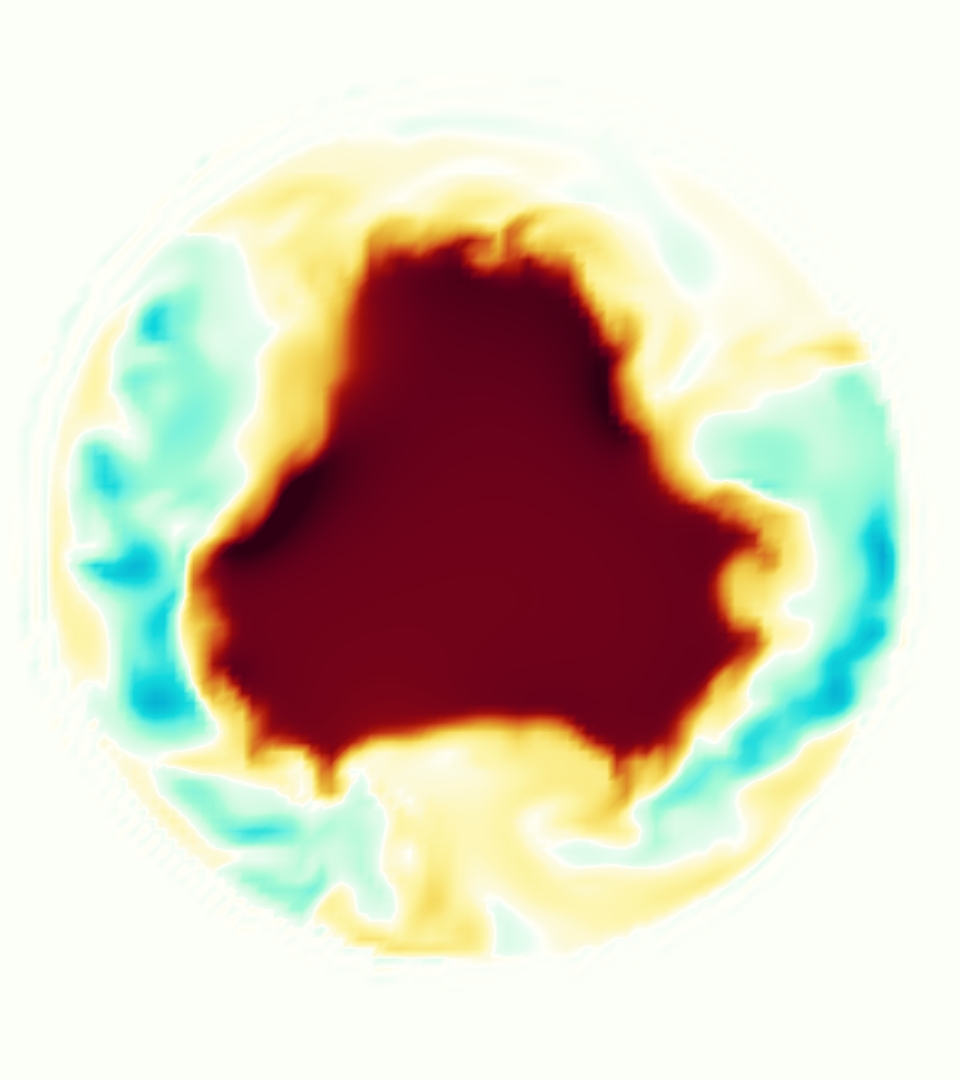

Slice views of the (axial) component of fluid velocity in the axial plane, orthogonal to the flow direction, show that the simulation replicated the development of the jet over the cardiac cycle. At each phase, the simulation matched the forward speed of the core of the jet and the locations of reverse flow back towards the valve annulus. While there are some differences in the shape of the jet at certain phases and locations, the simulation clearly produced the general dynamics of the cardiac cycle that are seen in the experiment.

At = 0, the axial slice directly at the valve annulus shown in columns 1 and 2 in Figure 6, there was excellent agreement between the simulation and experiment over the cardiac cycle in the speed and shape of the jet through the valve. In both cases, the axial velocity increased as the flow accelerated during systole and the valve leaflets opened, then decreased during diastole with slight negative velocity before the valve leaflets were fully closed. The forward flow through the valve annulus did not form a full circle, but rather developed a triangular shape with a point of the triangle forming along the interior curve of the vessel, at the bottom of the axial slices. At = 0, the points of this triangular jet shape aligned with the commissures of the valve. This shape persisted during peak systole and was well-matched by the simulation.

The axial slice = 0.625 cm, shown in columns 3 and 4 in Figure 6, cut through the support scaffolding of the valve and the leaflets when they are open. In the experimental data, the shape of the jet changed as it moved downstream. A triangular shape occurred, but the points were then aligned with the middle of each open leaflet as opposed to the commissures. Those points were also more rounded than they were at = 0. The peak velocity of the jet was faster at = 0.625 cm than at = 0, as the flow accelerated through the open valve leaflets. The simulation produced these features at = 0.625 cm. The triangular shape of the jet shifted similarly, and its speed increased compared to the upstream slice. As the flow decelerated into diastole, the jet shape remained roughly triangular but diminished in intensity before disappearing after valve closure.

The jet continued to develop at = 1.25 cm, an axial slice immediately downstream of the valve scaffolding and open leaflets, shown in columns 5 and 6 in Figure 6. In the experimental data, the points of the triangular jet shape extended further towards the vessel wall. In addition, regions of reversed flow developed in the locations downstream of the commissures, resulting in curved sides to the shape of the jet. Each tip of the jet was unique, due to variations in the individual leaflets in the physical bioprosthetic valve. These variations are apparent in the velocity fields, possibly because the jet edges are similar enough cycle to cycle that irregularities are still being captured even with phase averaging. Further discussion of these features can be found in Schiavone et al. [39], which showed that the jet tip shapes occurred in different pulmonary anatomies, demonstrating that they were likely due to inherent properties of each leaflet. The leaflets in the mathematical model of the valve are identical, so these nuances in leaflet variation could not be replicated. The simulation did capture some of the extension of the tips of the jet, as they were closer to vessel wall at slice = 1.25 cm than = 0.625 cm. The curves in the triangular sides of the jet were also present in the simulation, though they were less pronounced than the experimental data. At both = 0.625 cm and = 1.25 cm, the jet shape in the simulation was smoother than the jet in experiment. It is possible that the free edges of the leaflets in the mathematical model are not fully replicating the behavior of the physical leaflets of the bioprosthetic valve, in particular the amplitude or frequency of leaflet flutter, leading to the variations seen in the jet shape at = 1.25 cm downstream of the leaflet edges. The simulation, however, does capture the key features of the triangular shape and speed of the jet. Overall, qualitative comparisons demonstrated that the simulation reproduced key features of the flow during systole and diastole.

The and relative errors on the velocity magnitude and the component of velocity indicated quantitative agreement in the velocity field between simulation and experiment during systole (Table 1). We computed the relative error on the full domain and on the three slices 0, 0.625 and 1.25 cm. The relative error of velocity magnitude on the full domain ranged from 0.20-0.34. At all three slices, the relative error was below 0.37 through systole, and at peak flow was 0.25, 0.25 and 0.32 at 0, 0.625 and 1.25 cm, respectively. The relative error of the component on the entire domain was 0.36 at peak flow. At and = 0.625 cm, the relative error was below 0.29 through systole with values of 0.25 and 0.21 at peak flow, respectively. At cm, the relative error was 0.44 at peak flow. This error was larger than the error of the other slices, likely because there was more reverse flow that was not aligned between simulation and experiment at that slice. The relative error of velocity magnitude ranged from 0.27-0.41 over the full domain, and from 0.25-0.40 on the slices. At peak flow, errors were 0.38 on the full domain, and 0.29, 0.25 and 0.38 at slices at 0, 0.625 and 1.25 cm, respectively. On the component, errors ranged from 0.31-0.50 on the full domain, and 0.23-0.48 on the slices.

The integral metric indicated that the streamwise momentum of the jets in both simulation and experiment are very similar. The value of over the cardiac cycle is also shown in Figure 9 on the three slices 0, 0.625 and 1.25 cm. Values remained close between simulation and experiment throughout systole and diastole. In both simulation and experiment, the value of increases monotonically from the annulus slice at cm to the most distal slice at cm.